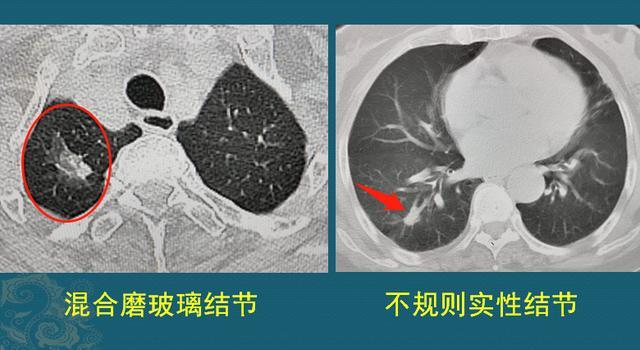

如何诊断肺癌 1 肺癌的分型和生长特点